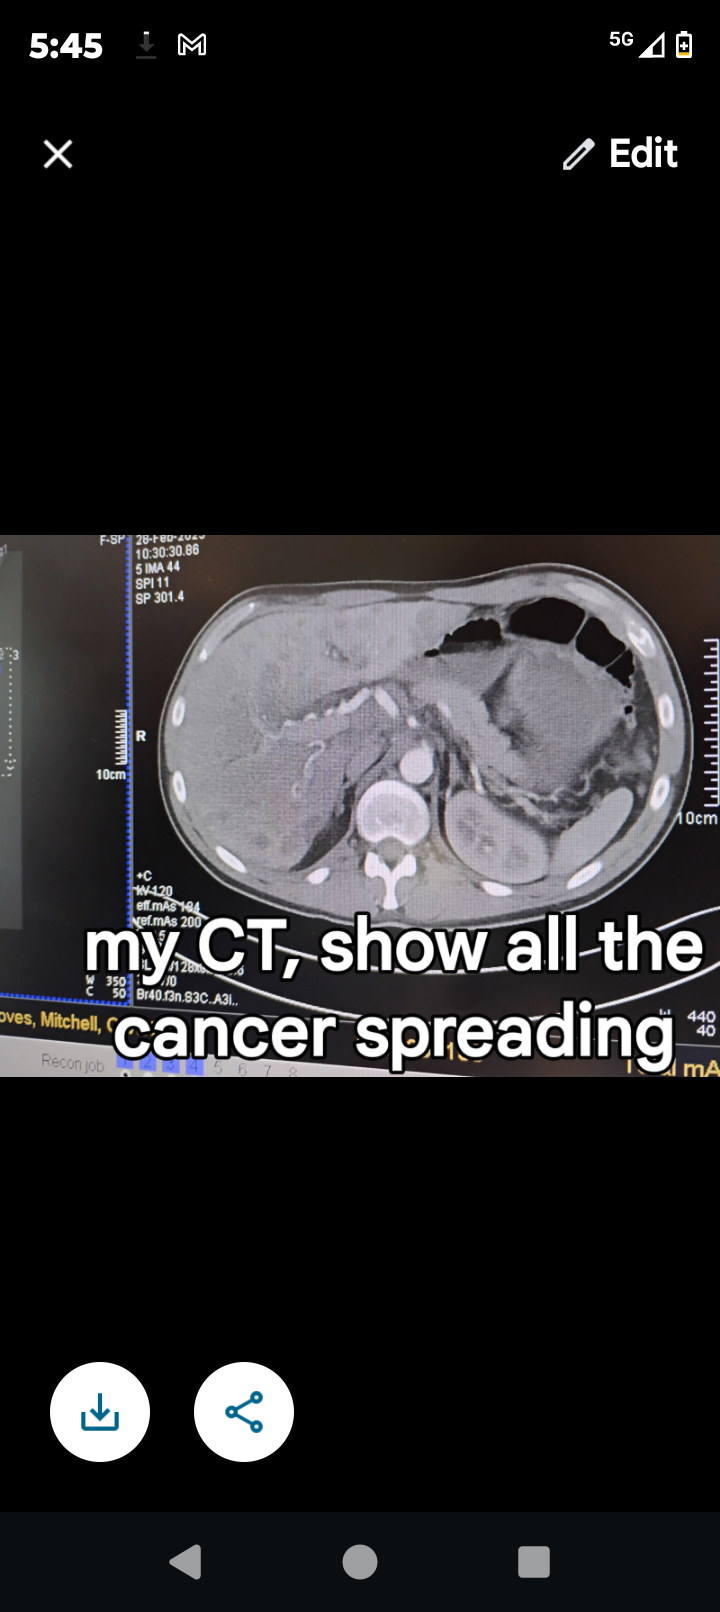

I recently been diagnosed but stage 4 liver cancer back in November of 2024.

I have been though hell and back, everyday fighting the severe pain that I must endure for the remainder of my life. I have went from 220lb to now 185lb. I have been going through chemo treatments for the past 4 months. I have been informed that the severe cancer I have has not been getting better but has been getting worse. I'm going to be doing 2 more chemo treatments before a revaluation, unfortunately the doctors has informed me that my potential life expectancy is something like 8 months to 1 year to live.